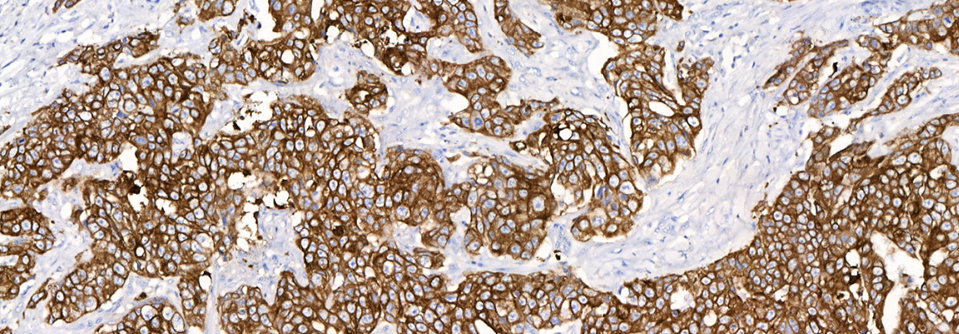

• Sharp & Well-Defined Staining

NeoPATH Pro sets a new standard in automated advanced staining for IHC, ISH, and FISH. Designed to meet your laboratory’s current staining needs while adapting to future demands, this advanced staining platform delivers high-capacity throughput, optimized reagents, and intuitive automation. Innovative features such as independent slide positions, integrated slide scanning, and Al assisted error prevention streamline workflows and enhance diagnostic confidence.